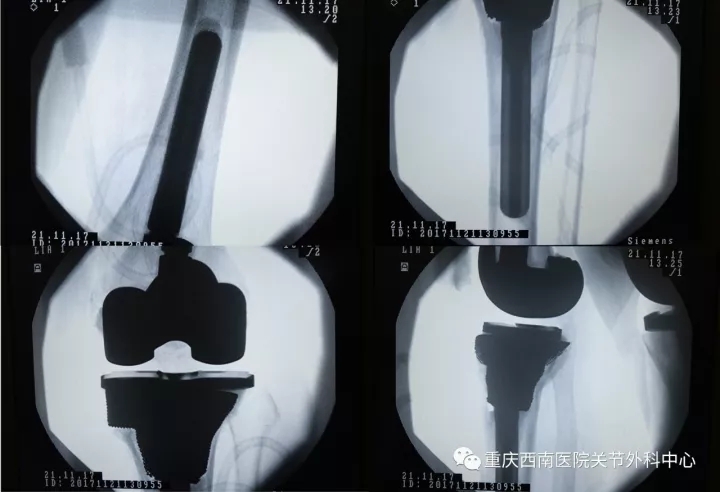

术后X光片

2017年11月21日12时32分手术按预期设计方案圆满顺利完成。正是由于医院与公司、医工合作为患者量身定制的3D打印钽金属补块良好的贴合度和表面粗糙度完美填充了巨大骨缺损,确保了骨缺损后钽金属假体植入的初始稳定性,表面粗糙多孔的金属骨小梁设计又可以使自体骨很快长入金属孔隙內,从而获得假体与自体骨的长期稳定,手术的操作流程大大简化,手术时间大幅缩减,并减少了手术并发症,也使得假体植入后的长期稳定性得到有效保证。